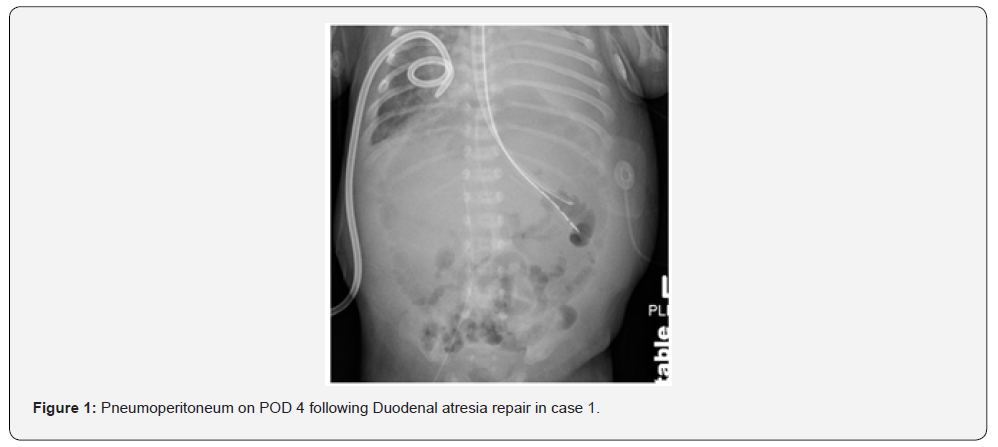

The first neonate, born at 31 weeks gestation with Trisomy 21, complete AVSD, pleural effusion, and duodenal atresia, was preoperatively on NI-NAVA. He was intubated for duodenal atresia repair and extubated to NI-NAVA on postoperative day two. On post-operative day four, he developed abdominal distention and hypoxemia; imaging revealed pneumoperitoneum (Figure 1). During laparotomy, worsening distention and hypoventilation prompted emergency abdominal drainage of gas and serous fluid. He required two doses of epinephrine and chest compressions briefly for bradycardia. A small anterior wall leak was repaired. Two months later, he underwent cardiac surgery and was eventually discharged home at six months of age. The second neonate, born at 37 weeks gestation and small for her gestational age, with duodenal atresia, myelomeningocele, and musculoskeletal deformities, underwent duodenal atresia repair where an annular pancreas was found. She was initially extubated to high flow nasal cannula, but within hours she required escalation of support to CPAP and then NIPPV. Seven hours post-extubation, she developed abdominal distension; imaging showed pneumoperitoneum (Figure 2). Re-exploration revealed a leaking anastomosis due to suture dehiscence, which was then repaired. She was successfully extubated to room air on postoperative day five and tolerated feeds.